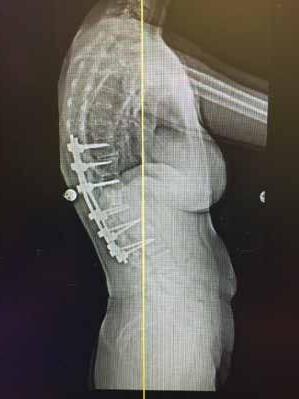

TOTAL DISC REPLACEMENT? TOTAL DISC

Total disc replacement (TDR) may be an alternative to spinal fusion for patients with cervical or lumbar herniated discs or degenerative disc disease.

The goals of total disc replacement surgery are to maintain segmental spinal motion, relieve pain, increase activity, restore disc height and proper spine curvature, and reduce post-operative recuperation time.

If you are experiencing neck or back pain and are considering surgery, isn't it worth your time to schedule an appointment with Dr. Jason E. Garber to nd out if motion preservation technology is an option for you?

Dr. Garber is one of Southern Nevada's most experienced spinal surgeons and a leader in arti cial disc replacement surgery.